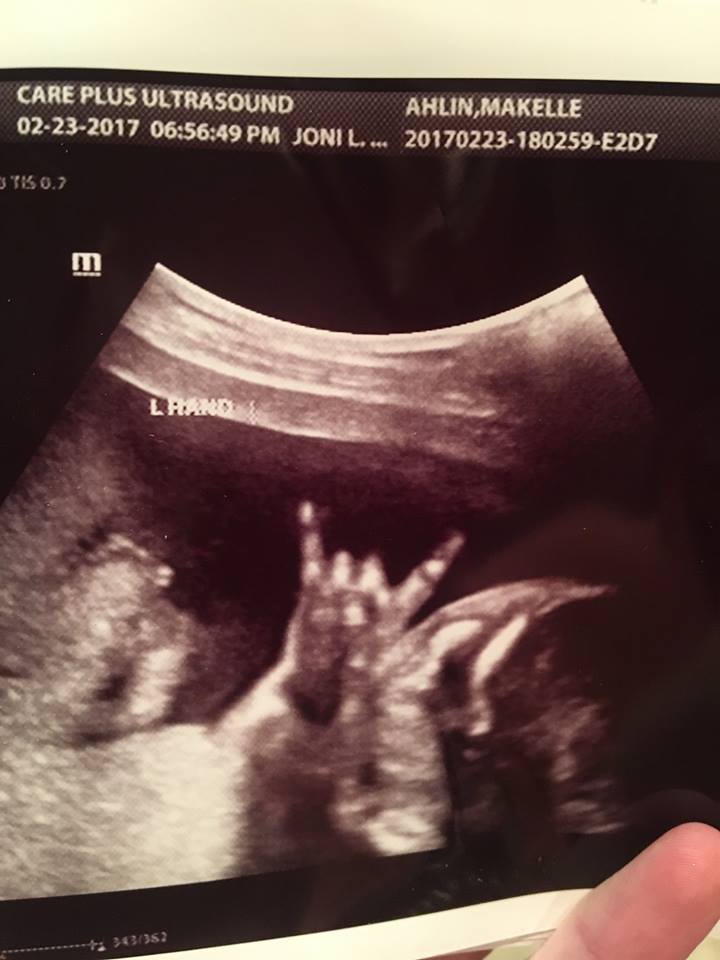

Hình ảnh siêu âm con của cặp đôi Jared và Makelle Ahlin

Mẹ Makelle cho biết em bé có vẻ thích nghe nhạc. "Tôi thường bật nhạc cả ngày khi ở nhà. Điều đó khiến tôi cảm thấy dễ chịu”.

Cặp vợ chồng đã xem đi xem lại video nhiều lần và rất phấn khích